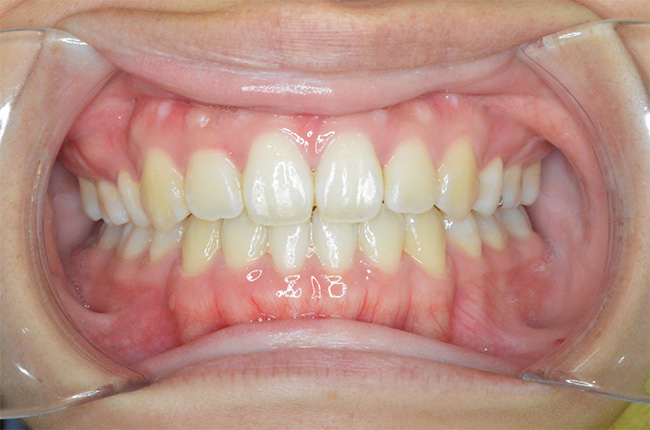

治療終了時